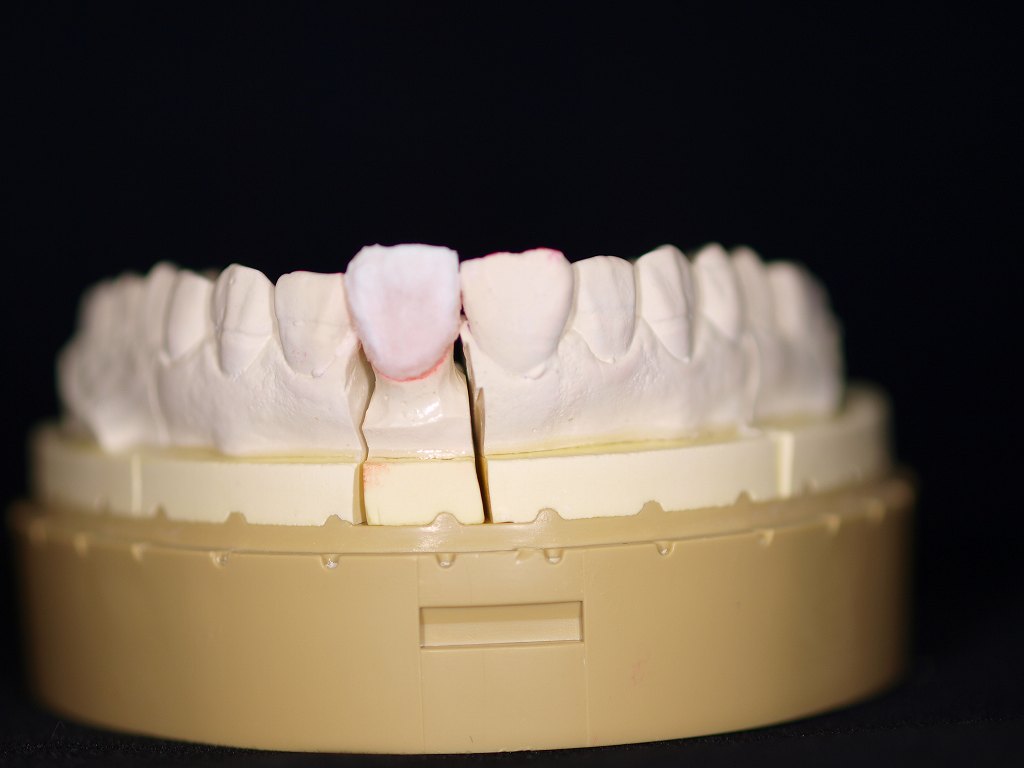

この左上1番をオールセラミックにて作成していきます

シェード合わせを行っていきます

完成したオールセラミックになります

このように完成しました

きれいな歯に塩上がっていますが、、

口腔内にて歯冠の幅径が広くならざるを得なく、咬合の

影響を受けてこのような形態に仕上がっています

理想的な歯に仕上げるには下前歯の咬合調整、左上2番の近心部に

CRなどで歯冠幅径を狭くする工夫が必要かもしれませんが、

歯をけずる行為もCR充填にも限界があります